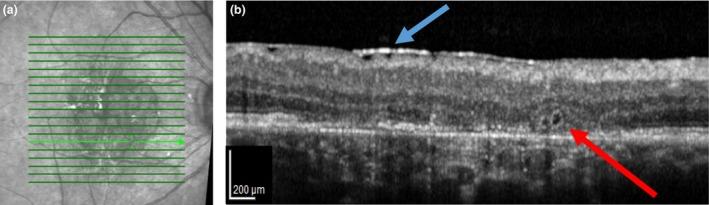

Cones are at great risk in a wide variety of retinal diseases, especially when there is a harsh microenvironment and retinal pigment epithelium is damaged. We provide established and new methods for assessing cones and retinal pigment epithelium, together with new results. We investigated conditions under which cones can be imaged and could guide light, despite the proximity of less than ideal retinal pigment epithelium.

We used a variety of imaging methods to detect and localise damage to the retinal pigment epithelium. As age-related macular degeneration is a particularly widespread disease, we imaged clinical hallmarks: drusen and hyperpigmentation. Using near infrared light provided improved imaging of the deeper fundus layers. We compared confocal and multiply scattered light images, using both the variation of detection apertures and polarisation analysis. We used optical coherence tomography to examine distances between structures and thickness of retinal layers, as well as identifying damage to the retinal pigment epithelium. We counted cones using adaptive optics scanning laser ophthalmoscopy. We compared the results of five subjects with geographic atrophy to data from a previous normative ageing study. Using near infrared imaging and layer analysis of optical coherence tomography, the widespread aspect of drusen became evident. Both multiply scattered light imaging and analysis of the volume in the retinal pigment epithelial layer from the optical coherence tomography were effective in localising drusen and hyperpigmentation beneath the photoreceptors. Cone photoreceptors in normal older eyes were shorter than in younger eyes. Cone photoreceptors survived in regions of atrophy, but with greatly reduced and highly variable density. Regular arrays of cones were found in some locations, despite abnormal retinal pigment epithelium. For some subjects, the cone density was significantly greater than normative values in some retinal locations outside the atrophy.